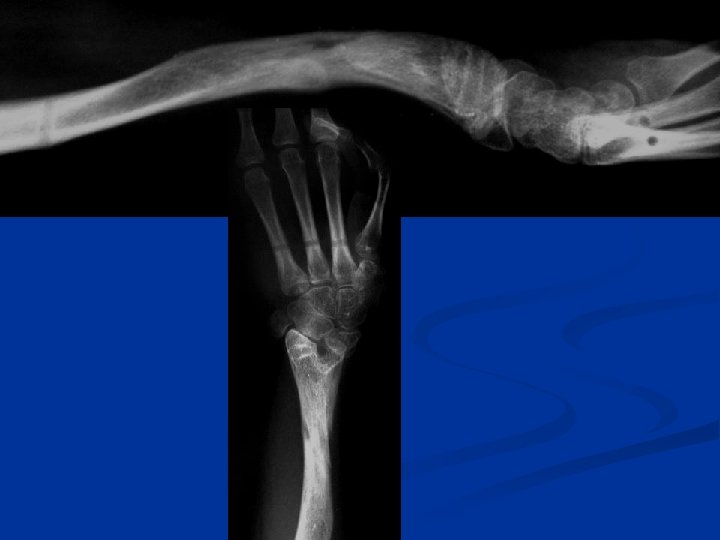

16 y Radial clubhand 1 y centralization 2 y pollicization

12 Feb 03 Osteotomy R ulna + application TSF Intraop Post-op

During distraction

4 months post op.